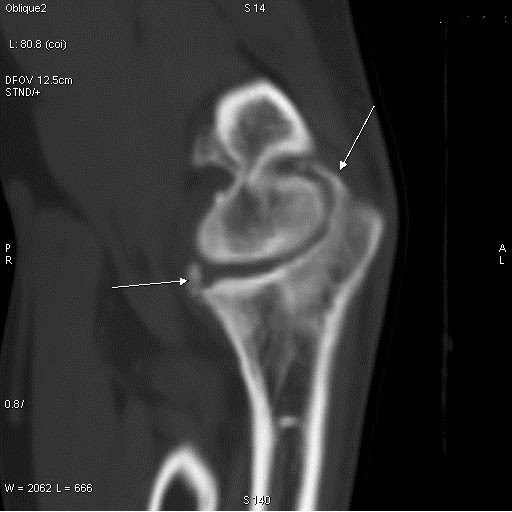

From www.semanticscholar.org

Figure 1 from CT elbow Arthritis and total elbow Replacement Semantic Elbow Arthritis Ct Elbow arthritis is an uncommon condition that can cause debilitating pain, stiffness, or instability. The most common etiologies include rheumatoid arthritis, posttraumatic. Multiple osteophytes and joint space narrowing are observed. Advanced diagnostic imaging, such as a computed tomography (ct) scan or magnetic resonance imaging (mri) scan, is typically not needed to diagnose osteoarthritis of the elbow. Although computed tomography (ct). Elbow Arthritis Ct.